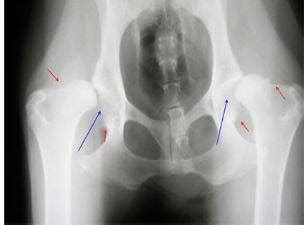

Dysplázia bedrového kĺbu - problém s pohybovým aparátom môže byť spôsobený dislokáciou stehennej kosti, ktorá nezapadá do bedrovej jamky. Následný pohyb psíkovi spôsobuje nepohodu. Podobný prípad môže nastať aj pri lakťovom kĺbe. Ochorenia srdca - vyskytujú sa rôzne defekty či abnormality vo funkcii kardiovaskulárneho systému. Ochorenia obličiek a močových ciest - u amerických stafordov sa zvyknú vo vyššej miere vyskytovať ochorenia močových ciest a obličiek. Typická je napríklad cystinúria, čo je defekt obličiek, pri ktorom sa vylučuje zvýšené množstvo aminokyselín. Hyperurikosúria sa zasa prejavuje nadmerným vylučovaním kyseliny močovej. Degeneratívna myelopatia - ide o nervové ochorenie miechy. Vyskytuje sa zvyčajne u starších psov. Príznakmi sú zhoršená stabilita a zlá koordinácia pohybov u jedinca. Nástup ochorenia je postupný, no časom postupuje a postihuje končatiny i svaly. Pes je paralyzovaný a nehybný, takéto štádium vedie často k smrti. Progresívna retinálna atrofia - ide o degeneráciu očných buniek na sietnici (čapíky a tyčinky). Cerebelárna ataxia - toto dedičné ochorenie postihuje mozoček jedinca. Ochorenie môže byť spôsobené nádorom, infekciou a u tohto plemena môže ísť taktiež o vrodenú poruchu. U psov sa prejavuje stratou koordinácie pohybov, trasením alebo neovládateľným pohybom a nakláňaním hlavy.